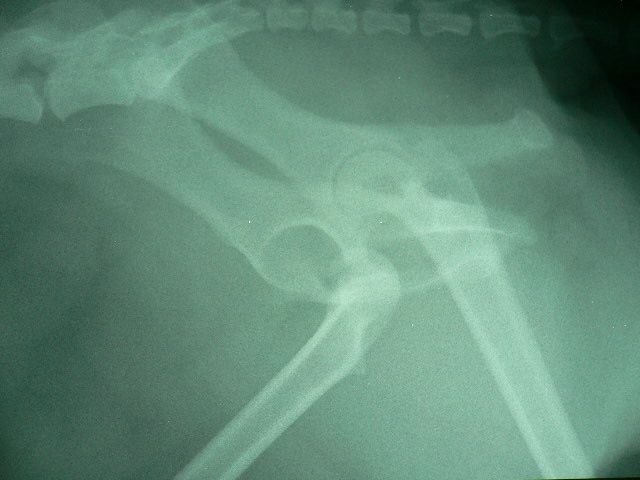

本日、テーピングを取るために鎮静処置を行いました。レントゲン写真で確認を行い、股関節が正常位置にキープされていることが分かり、煩わしかったテーピングを晴れて外すことができました。これから約2週間ほどは、引き綱をつけのリハビリが必要です。今度は、指示を守ってくれるのでしょうか?「あまりはしゃぎすぎると、また外れるョ〜!」